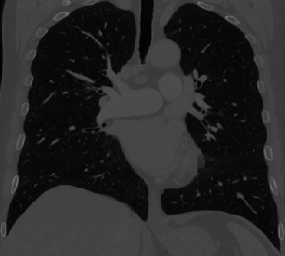

However, current state-of-the-art methods of lung organ segmentation still face several challenges and aspects for improvement. Firstly, the unlimited voxel values, multi-site imaging discrepancy and class imbalance in lung organ images can lead to false-negative and leakage issues in prior segmentation methods, which badly influences the critical early diagnosis of imperceptible lung diseases, e.g., lung fibrosis, nodule and hypertension, etc. Secondly, the presence of numerous slender branches, e.g., bronchioles and arterioles, which are easily lost during the recycled down/up-sampling procedure in Fig. 1, can result in discontinuity, detail loss, and coarse mask predictions. Thirdly, most CNN-based medical segmentation methods treat all points equally during the mask rendering stage, overlooking the vulnerability of border points in Fig. 1 (f) and the importance of explicit border modeling. Lastly, while Vision Transformer (ViT) has shown promise in computer vision tasks [1, 4], its quadratic operation complexity limits its application in 3D high-resolution CT images due to hardware constraints. Meanwhile, most specific datasets for medical image analysis are small and scarce due to laborious manual annotation and privacy protection, which badly restricts the potential of transformer-based top-tier methods.

We qualitatively analyze our method on four challenging lung organ datasets. In Fig. 5, SFCN [19] suffers from severe false positives and some false negatives, especially for the big green areas of airway leakages. WNet [22] is mainly influenced by false negatives on the main trachea. For the Fibrosis dataset at the third row, it also encounters the false negative problem in the terminal bronchioles moderately. FANN [10] bears the slight discontinuity issue of false negative in the terminal bronchioles of BAS dataset, and the severe discontinuity and airway leakage problems on the more challenging Fibrosis benchmark. Instead, due to the above two novel modules, our method can solve the defects of false negative, discontinuity, and leakages faced by past advanced methods. Besides, the results on PARSE22 artery dataset in supplementary Fig. 6 also proves this.